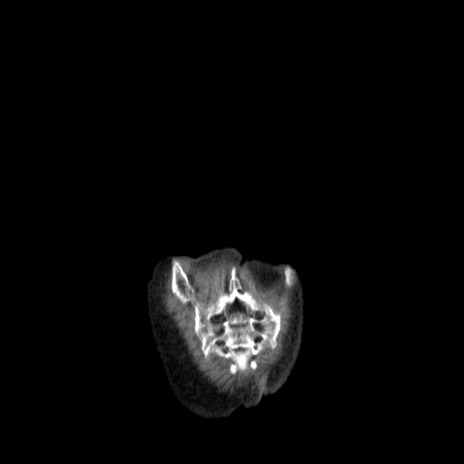

横断像